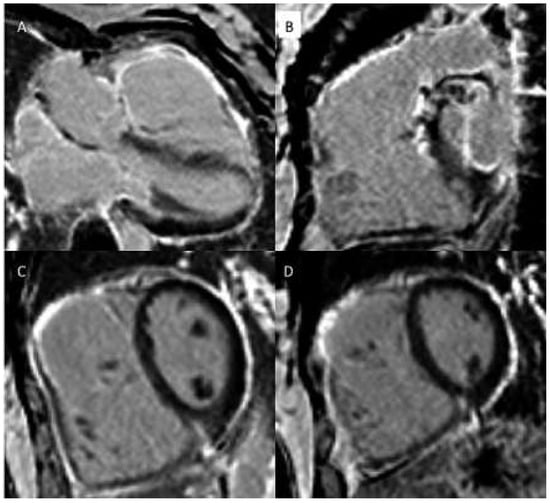

In infants / small children, spatial resolution can be increased by reducing the size of the voxels and increasing signal averages for more signal. For adequate recovery between inversion pulses, acquisition of every third of four heart beats (instead of every other heart beat) should be considered. Image acquisition should be kept short by using a turbo factor to avoid blurring. Reporting: left ventricle 17 segment model, right ventricle 9 segment model [28, 29] (for examples see Figure 4a,b).

Figure 4.

(a) Late gadolinium enhancement (LGE). 21-year-old patient with arterial switch for transposition of the great arteries (TGA) after postoperative myocardial ischaemia. Extensive area with subendocardial LGE in anterolateral segment (A) and in the inferior mid-ventricular segment (B). (b) Patient with transannular patch repair and VSD closure for tetralogy of Fallot and residual severe PR. LGE in RVOT aneurysm (A), LGE of the RVOT aneurysm and VSD patch area and inferior insertion point (RV hypertrophy) (B), LGE in the RV free wall (C−D).